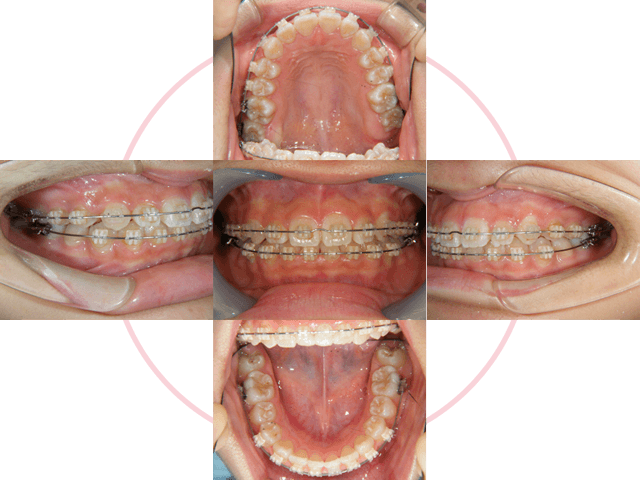

Case 01

下の前歯が、先天的に1本少ない患者さんです。上下の歯の本数が違うために、右上犬歯が八重歯になっています。

2

治療計画を立ててカウンセリング後、治療を開始します。ブラケットを歯に接着して、形状記憶合金のワイヤーを装着します。右上第一小臼歯を抜歯しています。

3

動的期間1年半で終了です。

4

ブラケットを外しました。上は着脱式の保定装置、下は前歯の裏側で保定しています。